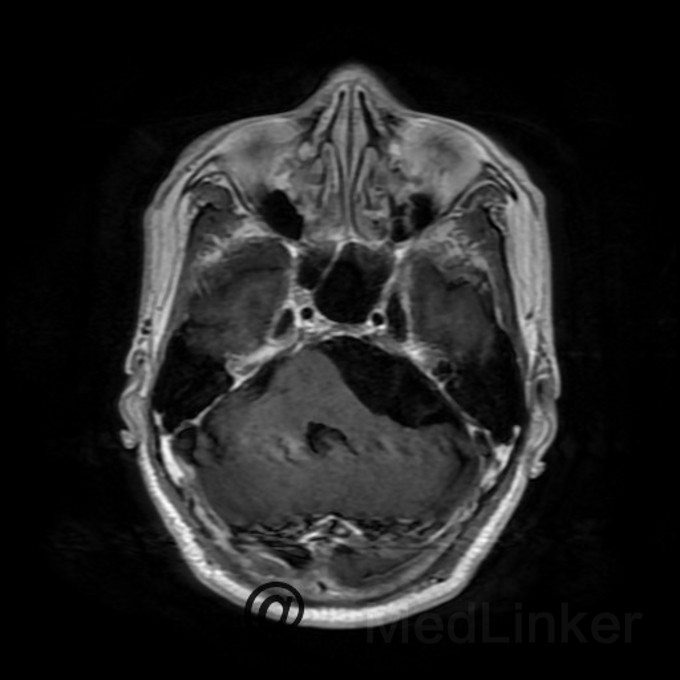

桥小脑区看到一个水样信号影?是蛛网膜囊肿还是表皮样囊肿?

蛛网膜囊肿还是表皮样囊肿都是囊肿,都是T1呈低信号,T2呈高信号,增强都木有强化,两者要怎么鉴别?求赐教

桥小脑区长T1长T2囊状病灶(如图),考虑表皮样囊肿还是蛛网膜囊